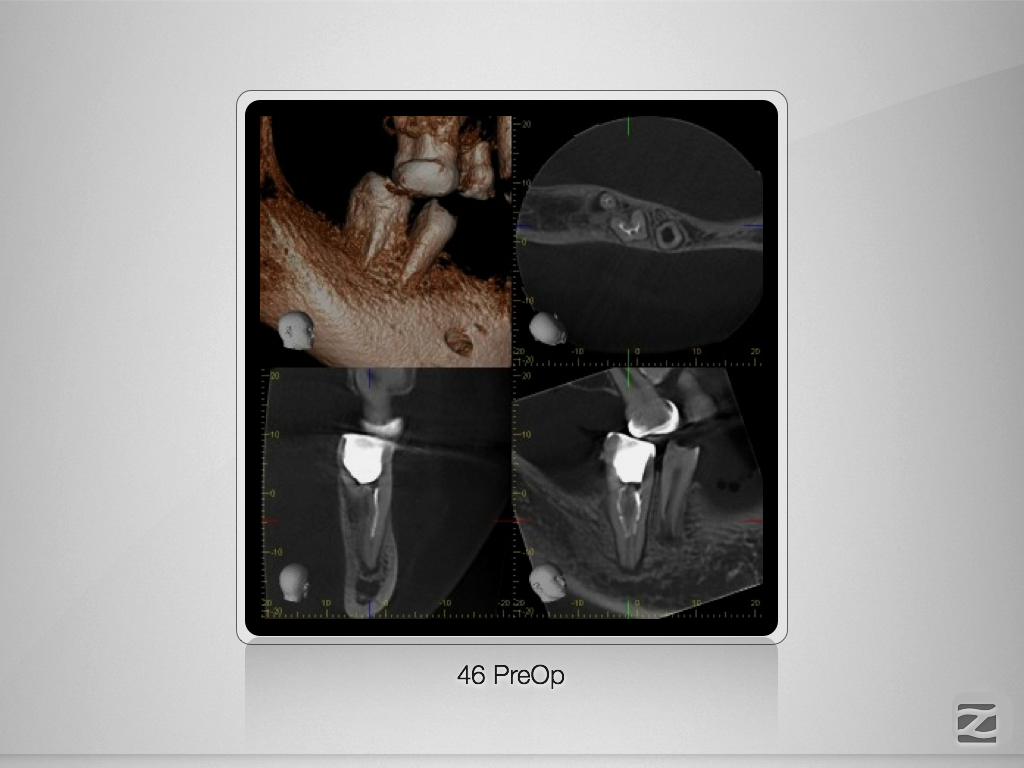

46D.004

Doppeltes C